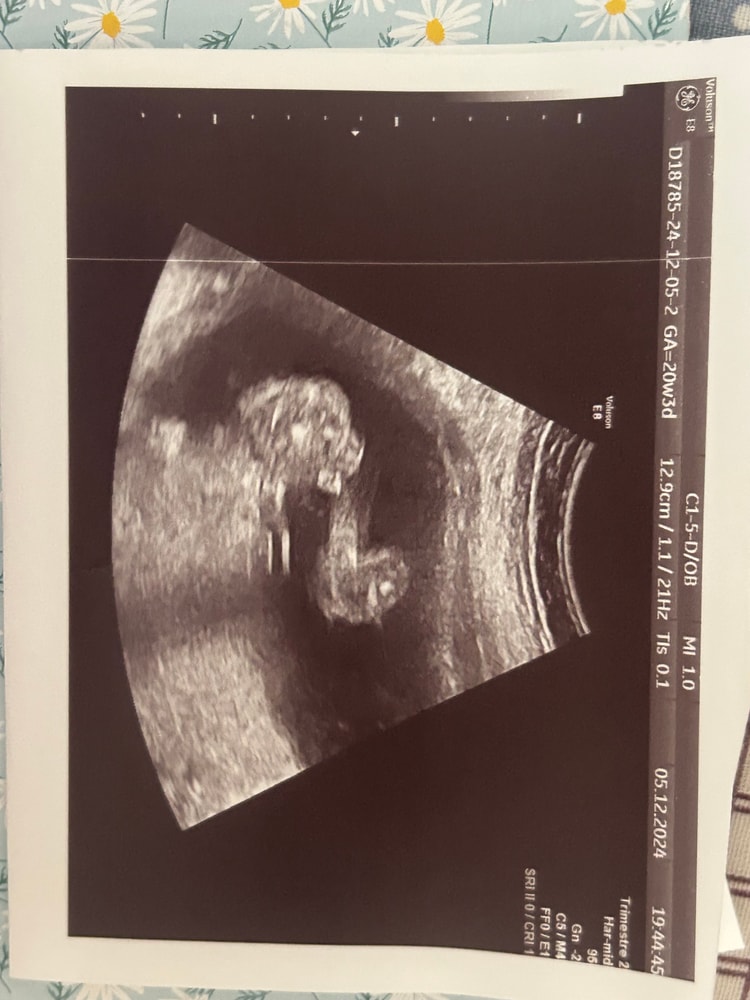

Arina в Клуб беременных 8 месяцев Пол малыша. Тут 20-21 нед🐣 Пол малыша Всем привет! Подскажите, пожалуйста 🙏🏻 это ведь мальчик? :) Посмотрите еще 20 записей на эту тему Лучший ответ Мама Лиля Пацан 23.03.2025 Ответить Отменить Ответить Лера Это мальчик 23.03.2025 Ответить Ольга На девочку похоже, если я правильно вижу))) 23.03.2025 Ответить Ольга Ольга , хотяяяяяя.... На последней фотке мальчик 23.03.2025 Ответить Сабрина я не разбираюсь, но интуитивно кажется что мальчик 🤔 23.03.2025 Ответить Лариса Тоже кажется, что мальчик. А врач кого предположил? 23.03.2025 Ответить Светлана По последней фотке- мальчик 23.03.2025 Ответить Пришел анализ на определение пола 😍 Пол ребенка Чаты Беременных Выберите чат: Январята-2026 Февралята-2026 Мартята-2026 Апрелята-2026 Майчата-2026 Июнята-2026 Июлята-2026 Августята-2026